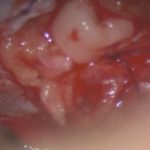

624

'25年4月

70代

後頭葉膠芽腫

頭蓋内腫瘍摘出術

No.’25_26 手術前1

No.’25_26 手術前2

No.’25_26 摘出 前

No.’25_26  摘出 中

No.’25_26 摘出 後